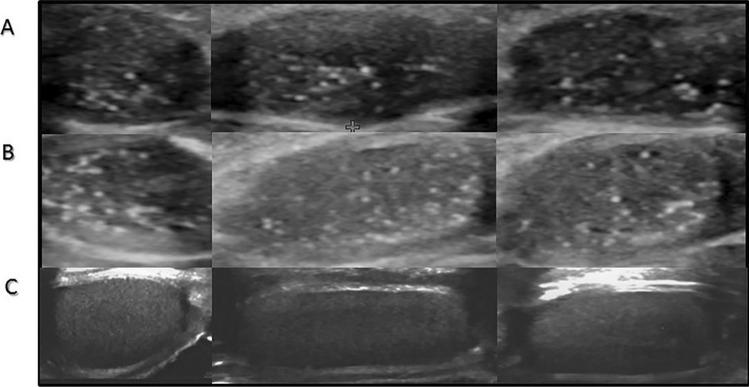

To present the results of testicular ultrasonography supported by clinical and hormonal aspects in paediatric patients with Klinefelter syndrome (KS). Prospective analysis of medical files of 20 patients diagnosed with KS between 2016 and 2022. Assessed data included analysis of causes of referral, ultrasound, and clinical characterisation with hormonal evaluation of serum FSH, LH, testosterone, inhibin B, and anti-Müllerian hormone. Non-mosaic Klinefelter syndrome (47, XXY) was diagnosed in 65% of cases (13/20) by the geneticist (including 7 cases prenatally), in 25% (5/20) by the endocrinologist and in 10% (2/20) by the hematologist. Ultrasound assessment revealed bilateral testicular microlithiasis (TM) in all patients. The youngest KS patient with TM was 3 months old. TM patterns have not changed during follow-ups of up to 6 years in any of the patients. In all KS patients markedly reduced echogenicity and in pubertal KS patients, also irregular echostructure of the testes was observed. The hormonal patterns observed in the study group were typical for those already described in KS. Sertoli and Leydig cell function was intact in prepubertal patients and deteriorated after the start of puberty.

Although the degenerative process in the testicular tissue starts very early in the testes in KS and is reflected in morphological changes seen in ultrasonography, Sertoli and Leydig cell hormonal function is normal in prepubertal KS patients.

• The morphological changes in the testes in KS may already be seen in early infancy.